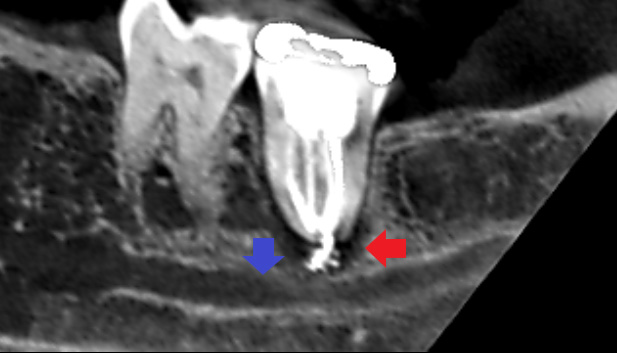

初診時のCT画像です。

赤い矢印の先に膿の黒い影がみられます。膿の影は、青い矢印の先にある太い下顎の神経に達し、この神経を圧迫し激痛を発していることが考えられました。